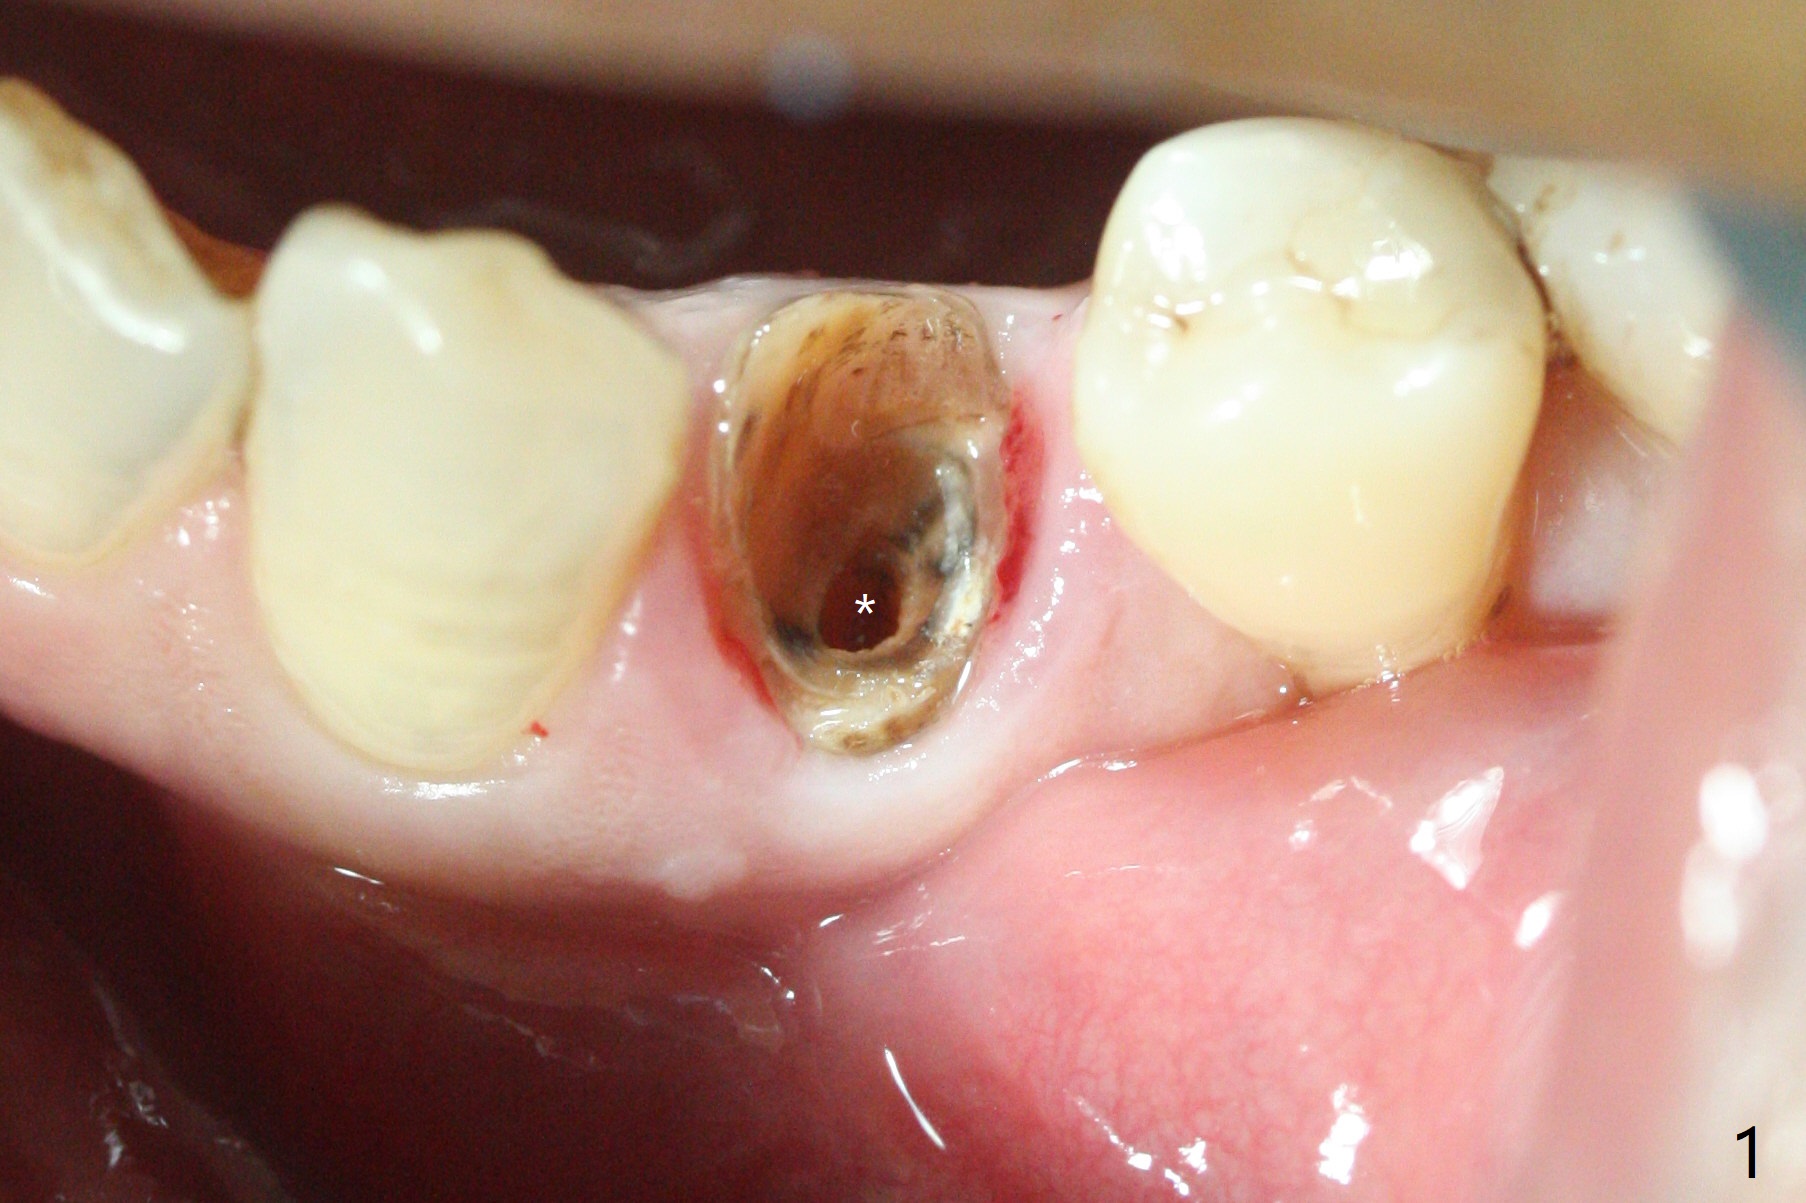

Three months post guide fabrication (coronavirus outbreak), the patient with loose post/crown returns for #21 extraction and immediate implant with guide (Fig.1 (*: post space)). In fact the root stump is flattened with diamond bur and 9 mm bone trimmer with guide before point drill. When the osteotomy finishes with 3.5x13 mm drill (under drilling with 10.5 mm offset), it has deviated buccal (Fig.2, 3,4); the outline of the bone trimmer mark is labeled by arrowheads in Fig.2. It appears that the center of the bone trimmer is dictated by that of the post space, as compared to Fig.1 *). When the root is removed except buccal shield (assuming that the deviation was due to the uneven surface of the root stump), the osteotomy is redone with guide, but remains buccal. Finally with buccal shield removal, a new lingual osteotomy is created free hand for a 4.5x11 mm implant (Fig.5) with 2-3 mm buccal gap for bone graft (Fig.6 * (literally)). In brief, bone trimmer also deviates according to resistance, basically irrelevant to the guide sleeve. The immediate provisional is intentionally removed 5 days postop to check whether a piece of gauze is retained in the socket as a gingival retraction cord for temporary crown fabrication; the buccal gap is kept with bone graft (Fig.7 *). No foreign body is in place. The margin of the abutment seems quite subgingival (Fig.8 *), but re-trimmed and polished provisional looks harmonious with the surrounding gingiva and the opposing dentition (Fig.9,10). The patient returns for prophy 2 months postop; the immediate provisional is removed for trimming and polishing. The bone graft seems to be integrated into a part of the gingiva (Fig.11 >). The abutment cuff appears to be too short.